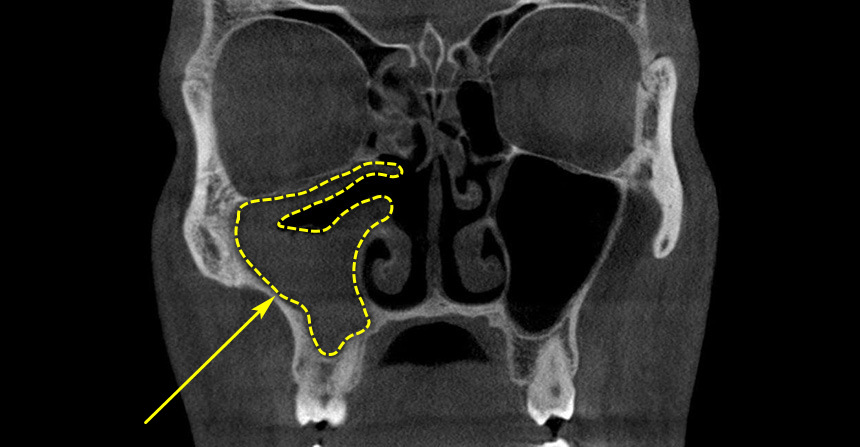

Як перевірити, чи є гайморит: перші ознаки й симптоми в дітей і дорослих